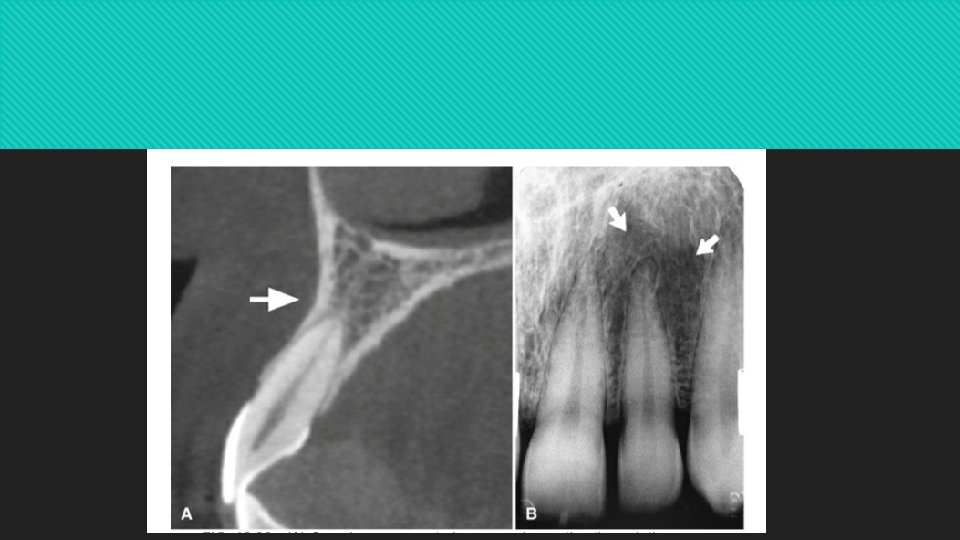

Alveolar Crest The gingival margin of the alveolar process that extends between the teeth is apparent on radiographs as a radiopaque line.

The level of this bony crest is considered normal when it is 0. 5 to 2 mm apical to the cementoenamel junction of the adjacent teeth The alveolar crest may recede apically with age and show marked resorption with periodontal disease

In the anterior region, the crest is reduced to only a point of bone between the closeset incisors Posteriorly it is flat, aligned parallel with and slightly below a line connecting the cementoenamel junctions of the adjacent teeth

The crest of the bone is continuous with the lamina dura and forms a sharp angle with it. Rounding of these sharp junctions is indicative of periodontal disease.